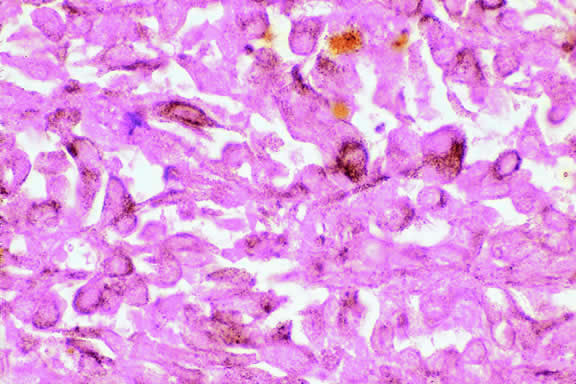

Varying degrees of necrosis may be found (Figs. 37 and 38). Necrosis tends to be more prominent in rapidly growing high-grade tumors or tumors that have had prior brachytherapy. The necrosis may be patchy and focal or may involve extensive parts or even all of the tumor. Aggregates of melanophages typically are found in the necrotic areas. Total infarction of the tumor (and other intraocular structures) may occur in eyes with severe secondary closed-angle glaucoma. As mentioned previously, melanocytoma is prone to spontaneous necrosis. The latter diagnosis should always be considered when a totally necrotic, heavily pigmented tumor is found.

Fig. 37. Focus of necrosis in choroidal melanoma. Pigmented melanophages have accumulated at interface between viable tumor and necrotic focus (below). (Hematoxylin-eosin, × 100.)

Fig. 38. Necrotic uveal melanoma. The cells of this necrotic melanoma are eosinophilic because they have lost their basophilic nuclear DNA. The cell type of a necrotic melanoma often can be ascertained if careful microscopy with an oil-immersion lens is performed. Necrotic uveal melanomas tend to behave clinically like mixed cell type melanomas. (Hematoxylin-eosin, × 250.)